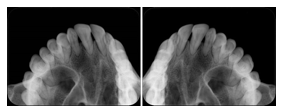

Cephalometric Series Structured Display

Figure OO-2. Cephalometric Series Structured Display